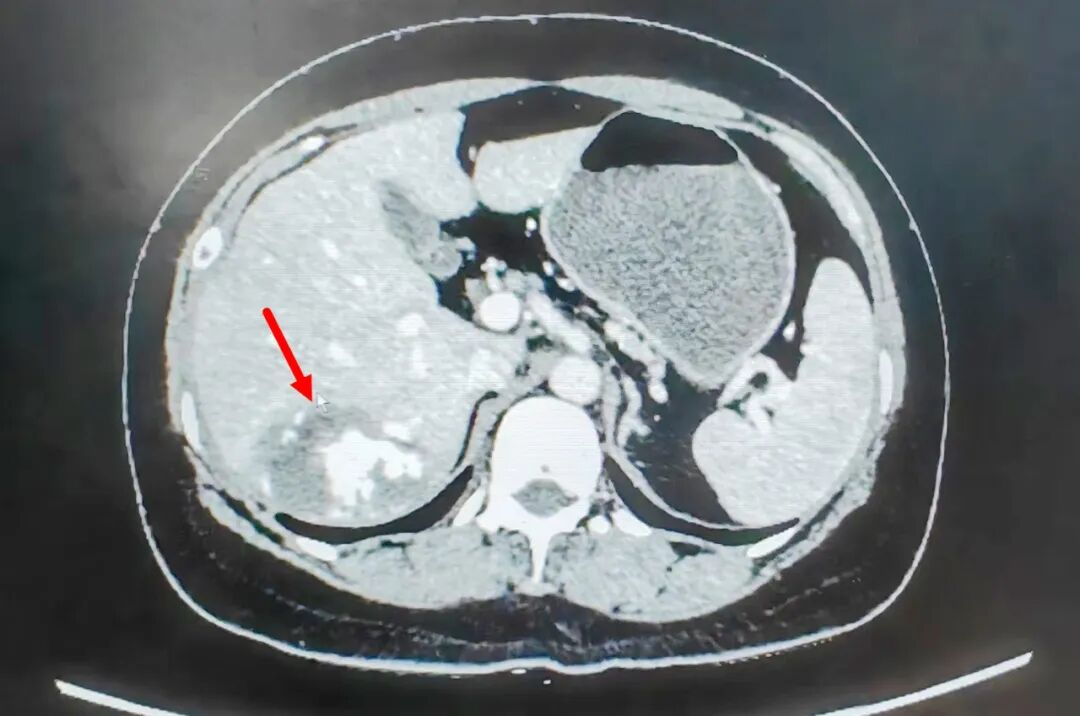

▲肝多发海绵状血管瘤

如今,在肝胆胰外科和甲状腺外科像王阿姨这样的案例越来越多,肝血管瘤是肝脏里长了一团异常的血管,它本质上是一种血管畸形,因其大部分主要由扩张的血管组成,形状像海绵,故此也常常被称为“肝海绵状血管瘤”。大多数肝血管瘤无明显症状,通常在体检(如B超、CT)时偶然发现。然而,当血管瘤长大到一定程度时,可能会引起上腹部隐痛或胀痛,部分能够在腹部摸到包块,极少数情况下可能出现瘤体破裂出血危急生命。大多数肝血管瘤不需治疗,定期复查即可,但出现以下情况时可能需要手术干预,如:血管瘤直径大于10厘米,上腹部疼痛、饱胀感明显, 血管瘤每年增长大于2厘米、疾病诊断无法明确时。若需治疗,只要适合微创手术,通过肝胆胰外科和甲状腺外科医护团队精准的围手术期管理,都能够让患者感受到“小切口、早出院、舒适养”的快速康复理念,从过去的术后卧床时间7至10天缩短到24小时内,平均住院日从10天以上降至4至7天,大幅提升了患者满意度。